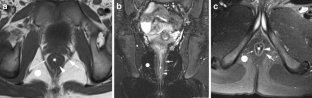

Perianal disease in pediatric Crohn disease: a review of MRI findings

Perianal complications of Crohn disease are a common occurrence in children and can result in significant morbidity when not accurately characterized prior to surgical intervention. MRI is an excellent imaging modality for the evaluation of perianal inflammatory bowel disease – allowing characterization and detailed description of perianal fistulas. MRI has many advantages over other imaging modalities for the pediatric patient. Radiologists will benefit from a sophisticated understanding of perianal anatomy, the classification of perianal fistulas, the advantages MRI offers in characterization of perianal fistulas as well as the common and incidental findings that are important in the MRI evaluation of perianal inflammatory bowel disease in children. Perianal fistulas are found at a high rate in pediatric referrals and are more commonly found in male patients.